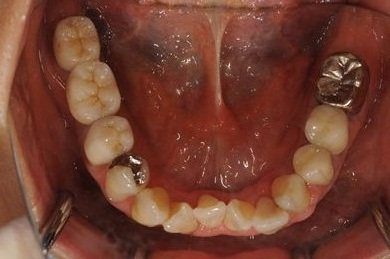

抜歯即日スピードインプラント+セラミック治療

| 性別/年齢 | 女性 / 52歳 | ||||||||||||||||||||||||||||||||

| 治療内容 | インプラント2本(抜歯即日スピードインプラント)、ハイブリッドセラミッククラウン5本(セラミック用土台2本)、ハイブリッドセラミックインレー1本 | ||||||||||||||||||||||||||||||||

| 総治療費 | 1,052,783円 | ||||||||||||||||||||||||||||||||

| 治療期間 | 1年3ヶ月 |